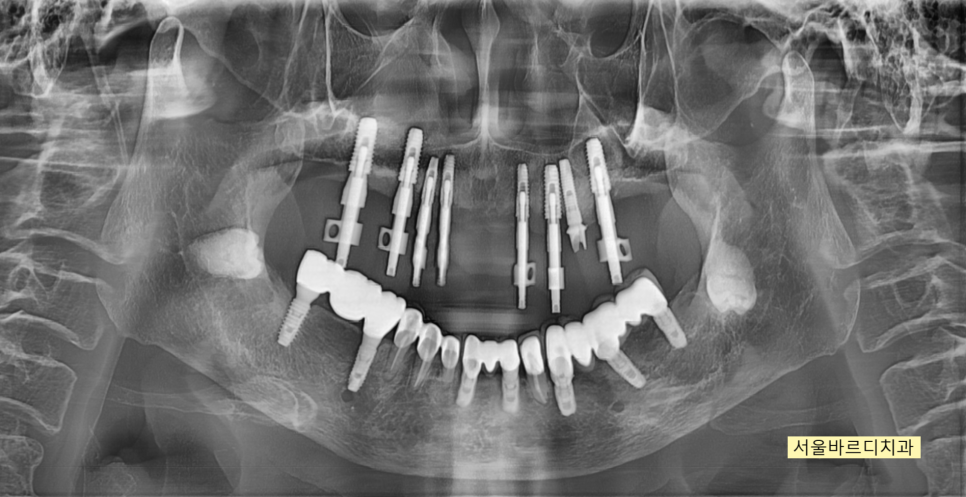

뽄을 뜨고 보철을 만드는 과정에서

위 아래 높이를 올려 마무리 하였습니다.

250324

치료 과정에서

기존에 심겨진 임플란트는 최대한 활용하였습니다.

높이가 낮아졌다하면

기존 임플란트를 제거해야한다 생각하시는 분들이 있으시더라고요~

임플란트는 뼈 안에 식립되어있고

높이를 올리는 것은 보철을 통해 해결해주기 때문에

문제가 되지 않습니다.

250314

치료가 끝난 모습입니다.

윗니가 아랫니를 덮는

정상적인 교합으로 마무리 되었습니다.